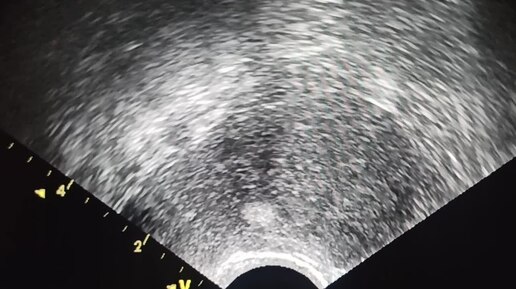

Начинающим врачам УЗИ: аденомиоз и мелкие миомы